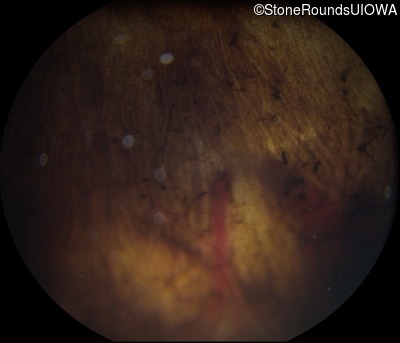

Fundus Photography - Left - 20/20 -1

Exemplar